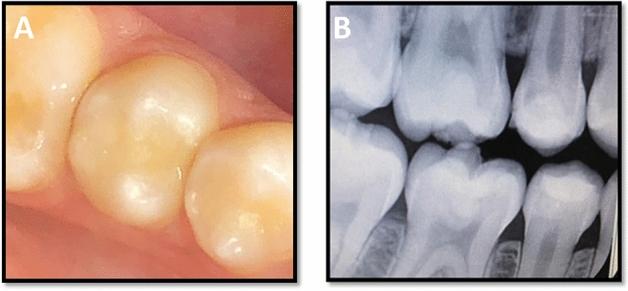

To evaluate the impact of using ion-releasing liners on the 3-year clinical performance of posterior resin composite restorations after selective caries excavation with polymer burs. 20 patients were enrolled in this trial. Each patient had two deep carious lesions, one on each side of the mouth. After selective caries removal using polymer bur (PolyBur P1, Komet, Brasseler GmbH Co. KG, Lemgo, Germany), cavities were lined with bioactive ionic resin composite (Activa Bioactive Base/Liner, Pulpdent, Watertown, MA, USA) or resin-modified glass ionomer liner (Riva Light Cure, SDI, Bayswater, Victoria, Australia). All cavities were then restored with nanofilled resin composite (Filtek Z350XT, 3M Oral Care, St. Paul, MN, USA). All the tested materials were placed according to the manufacturers' instructions. Clinical evaluation was accomplished using World Dental Federation (FDI) criteria at baseline and after 6 months, 1, 2, and 3 years. Data were analyzed using Mann-whitney U and Friedman tests (p < 0.05). The success rates were 100% for all resin composite restorations either lined with ion-releasing resin composite or resin-modified glass ionomer liner. Mann-whitney U test revealed that there were no statistically significant differences between both ion-releasing lining material groups for all criteria during the follow-up periods (p > 0.05). Resin composite restorations showed acceptable clinical performance over 3 years either lined with bioactive ionic or resin-modified glass ionomer liners after selective caries excavation preserving pulp vitality. After the 3-year follow-up period, Activa Bioactive and Riva Light Cure liners were clinically effective and they exhibited with the overlying composite restorations successful clinical performance.Trial registration number: NCT05470959. Date of registration: 22/7/2022. Retrospectively registered.